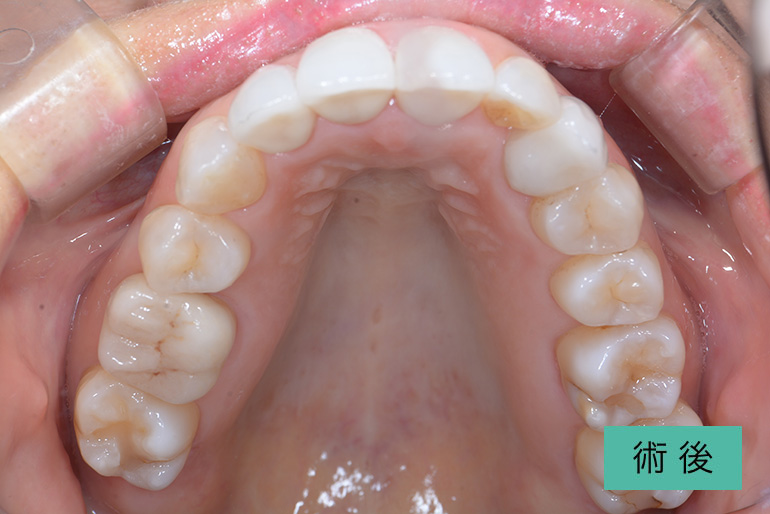

オールセラミック②

| 治療内容 | 上顎前歯右上3番から左上3番のセラミック冠 |

|---|---|

| 治療期間・回数 | 約1ヶ月、3回 |

| 費用(税込) | ¥990,000(165,000/1本)(補綴費用) ※自由診療 |

| リスク・副作用 | 疼痛、補綴物の脱落、咬合違和感、破折 |